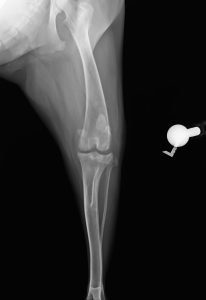

術前 レントゲン画像

TPLO像

ラテラル像